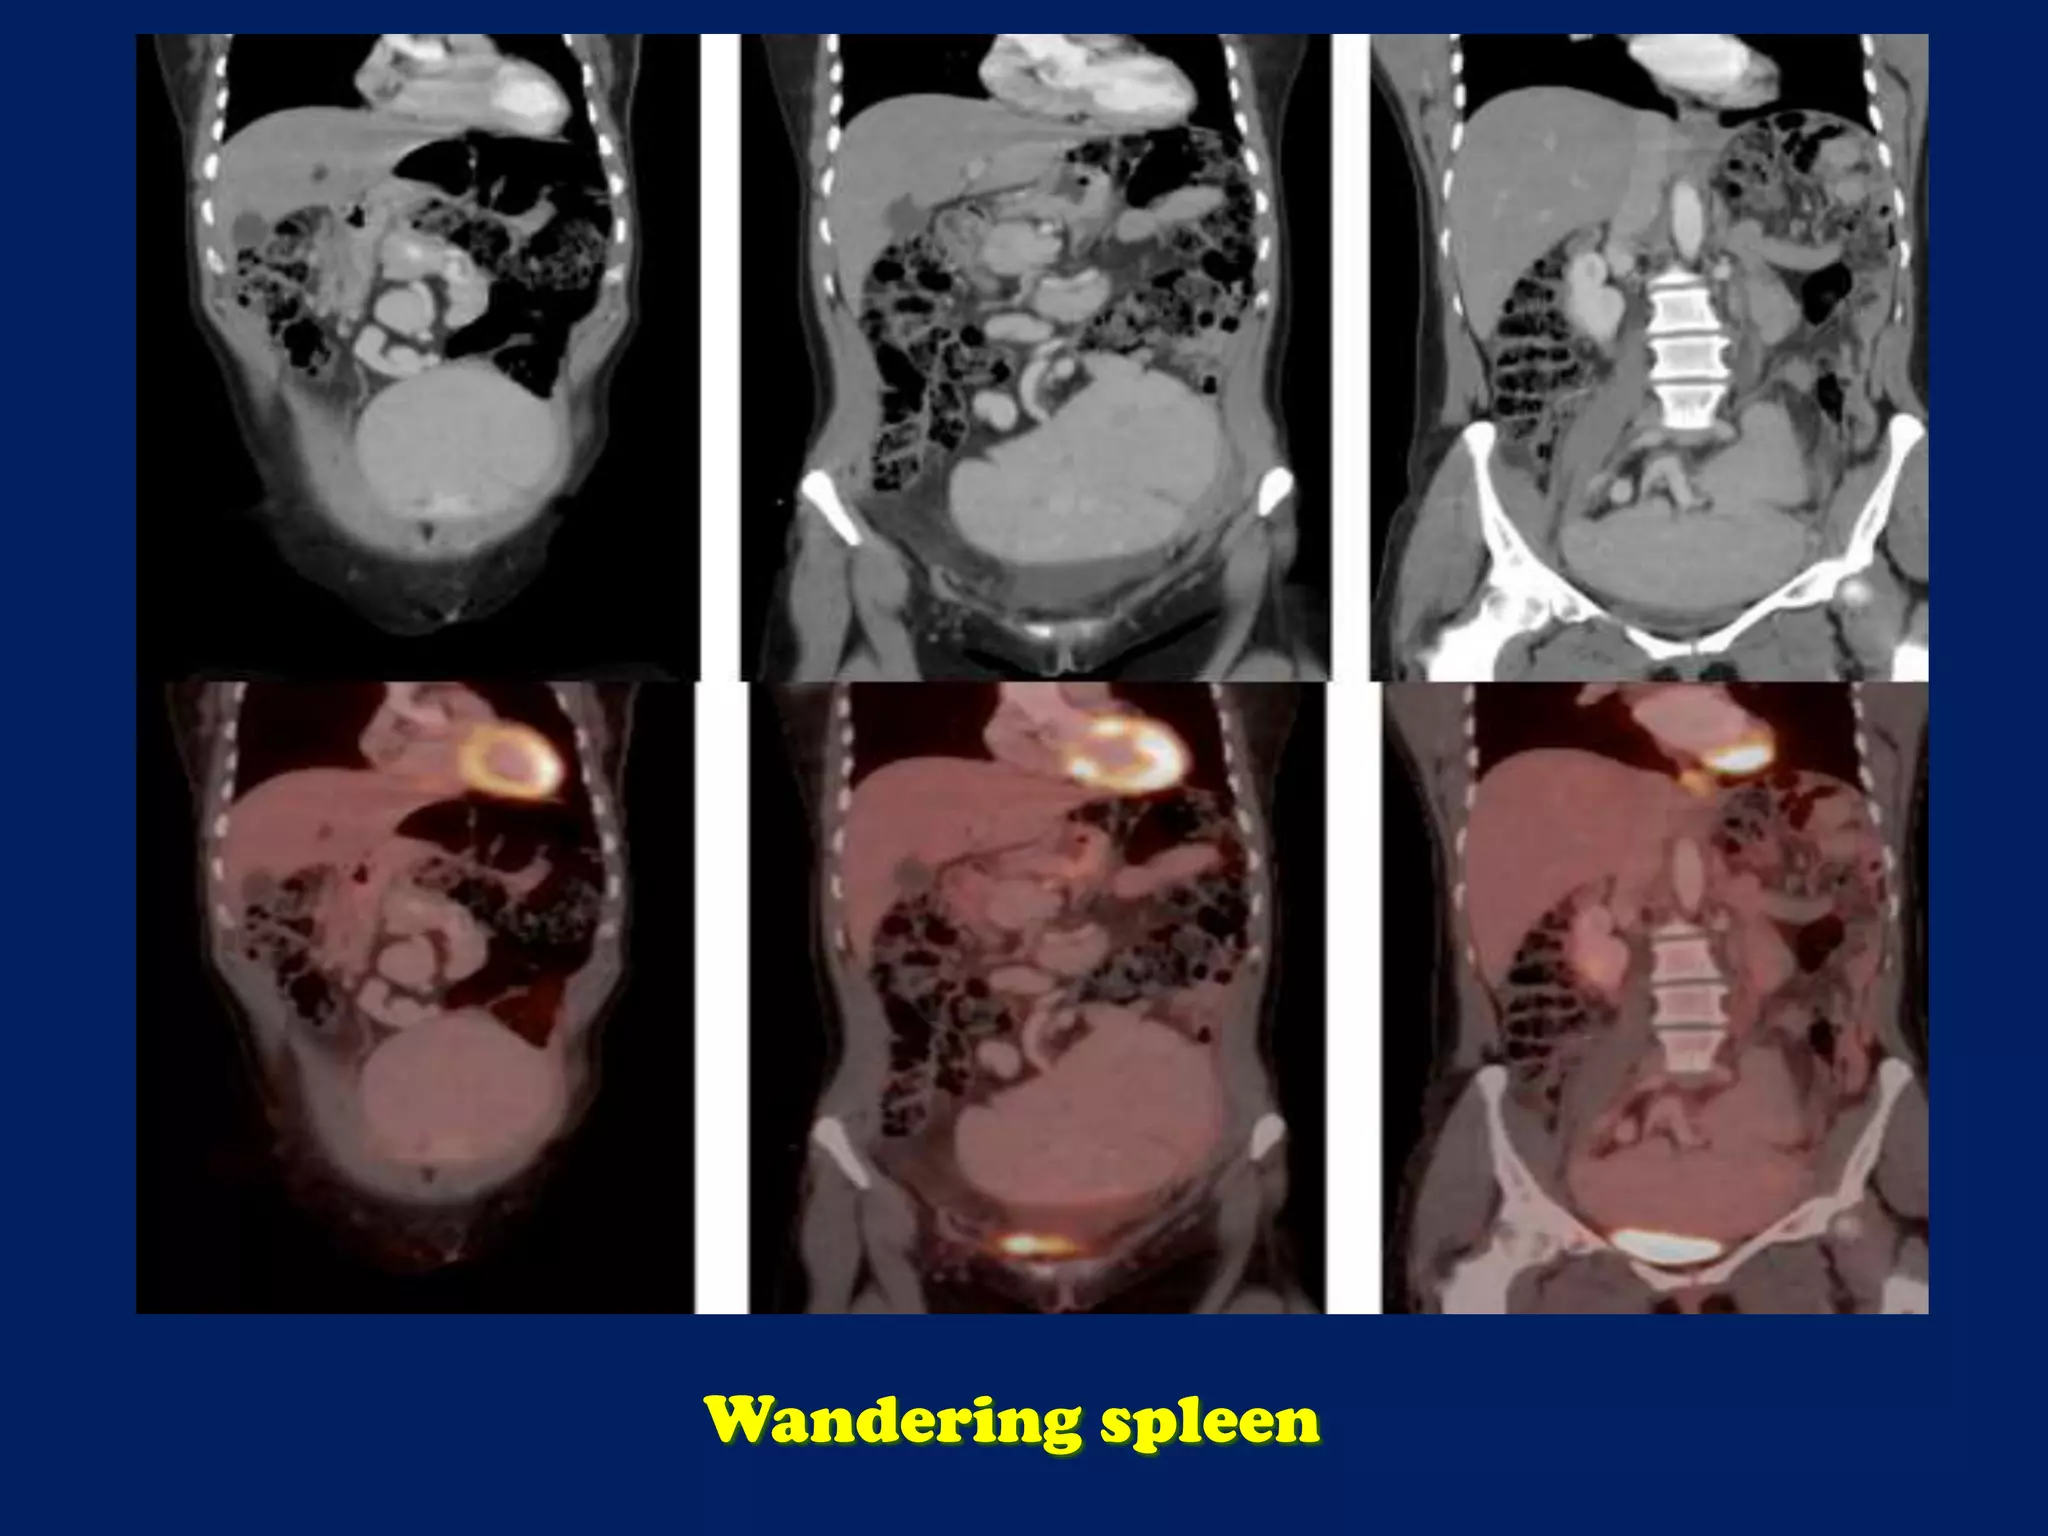

![Axial reconstructions derived from the CT portion of the PET/CT demonstrate the

‘whorled-appearance’ of the long vascular pedicle extending to the ectopic spleen.

The alternating bands of hypodensity and hyperdensity represent the splenic

vessels and surrounding fat of the twisted splenic pedicle. [red arrow = splenic

artery; yellow arrow = pancreas; white arrow = splenic vein; asterisk = spleen]

Wandering spleen](https://image.slidesharecdn.com/presentation1-140322130213-phpapp01/75/Presentation1-pptx-spleen-21-2048.jpg)

This document discusses imaging of the spleen and summarizes various congenital anomalies and pathologies that can affect the spleen. Some common congenital anomalies mentioned include accessory spleens, asplenia, polysplenia, and splenic fusions. Acquired conditions like repeated infarctions, infiltration, tumors, and cysts can also cause splenomegaly or functional asplenia. Wandering spleen is discussed as a rare congenital anomaly where the spleen lacks attachments and is mobile within the abdomen. Various grades of splenic lacerations and examples of splenic imaging findings are also briefly summarized.